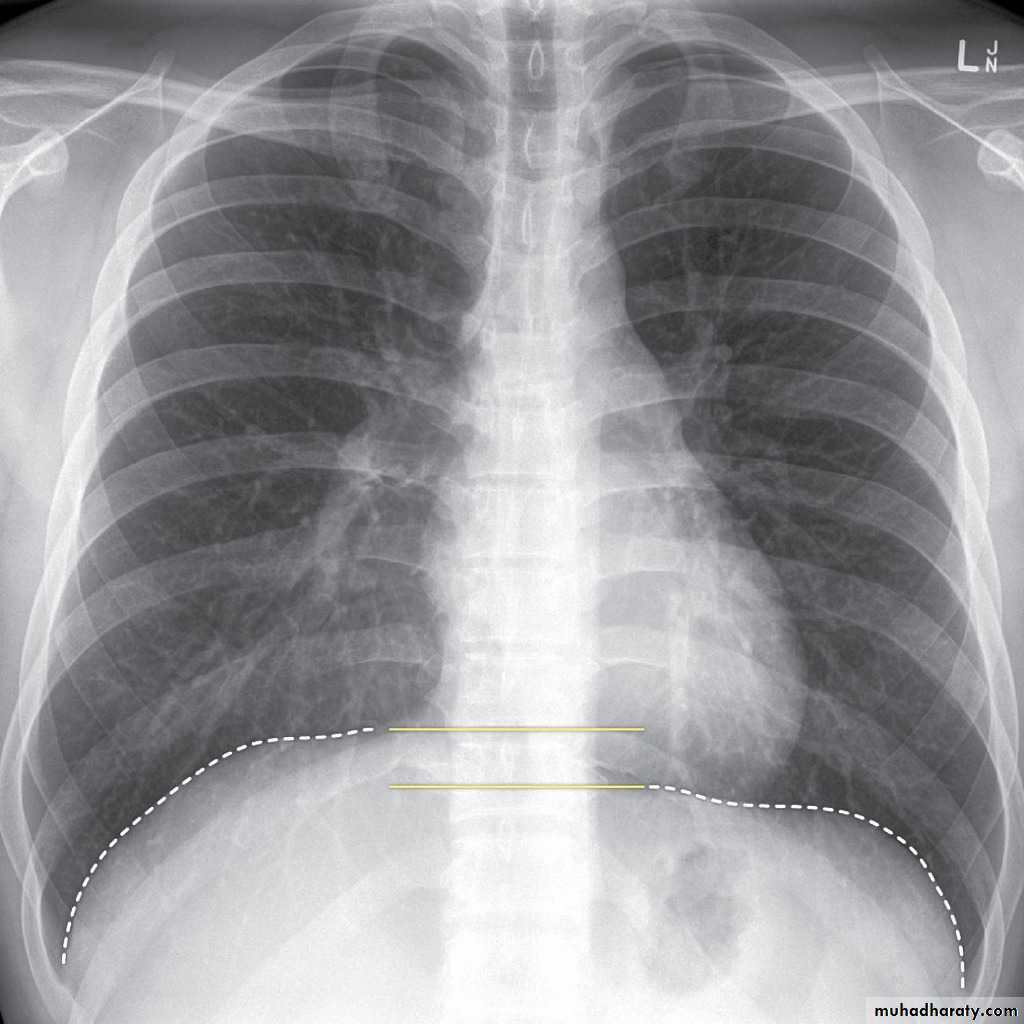

Look carefully on both diaphragmatic cruse costo & cardio phrenic angles

Don't forget to use rib in asses lung Zones

Pleural effusion

50.pleural effusion

51.pleural effusion .